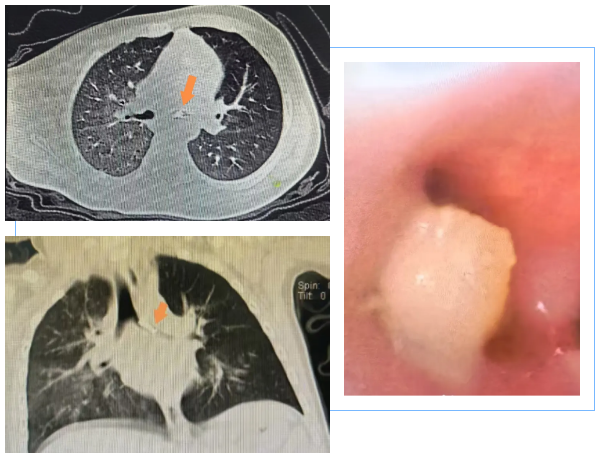

近日,黔南州中医医院儿科团队凭借精湛医术,成功为一名1岁7个月的幼儿乐乐(化名)完成高难度支气管镜手术,取出一枚藏匿于其左主支气管内近1年的骨性异物。困扰乐乐近一年的反复喘息、咳嗽症状,在术后瞬间缓解,小家伙终于摆脱了“假哮喘”的折磨,重获畅快呼吸。

据悉,乐乐近一年来被反复喘息、咳嗽困扰,家长带着孩子辗转就医,接受常规止咳、平喘治疗后,症状始终时好时坏,无法根治,严重影响孩子的正常生长发育和日常生活。直到家长带乐乐来到我院儿科就诊,经过儿科专家详细问诊、体格检查及胸部CT检查,高度怀疑其气道内存在异物,最终通过支气管镜检查得以确诊。

手术中,在高清内镜的引导下,小心翼翼地探查气道深处,精准定位异物位置,最终成功将这枚藏匿近一年的骨性异物完整取出。术后,乐乐恢复顺利,喘息、咳嗽症状彻底消失,精神状态明显好转,目前已顺利康复出院。

专家强调,一旦高度怀疑支气管异物,支气管镜检查是明确诊断与治疗的关键手段。该技术可直接探查气道深处,清晰显示异物的位置、形态和大小,同时能在直视下将异物安全取出,实现“诊断+治疗”一步到位,无需开胸手术,具有创伤小、恢复快的优势,是解决儿童气道异物问题的核心诊疗方式,其临床价值不可替代。